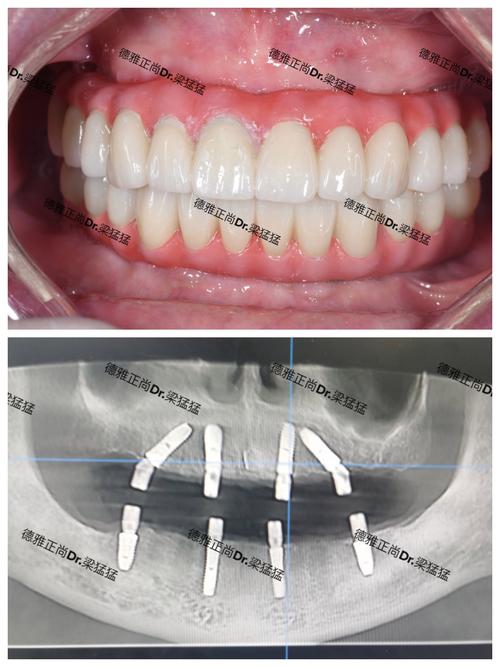

植得口腔的矫正案例库覆盖儿童、青少年及成人各类错颌畸形,从简单的牙列拥挤到复杂的骨性开颌,均取得了良好效果,12岁的患儿因“牙列拥挤伴上颌前突”,通过早期干预(扩弓+前方牵引),引导颌骨正常发育,避免了成年后正颌手术;35岁成人患者因“牙齿稀疏伴中线偏斜”,采用隐形矫正关闭间隙,调整中线,同时改善“凸嘴”问题,侧貌轮廓更柔和;45岁患者因“牙周病导致的牙齿移位”,通过正畸联合牙周治疗,排齐牙齿的同时稳定牙周组织,恢复了正常咀嚼功能,这些案例不仅体现了植得口腔的技术实力,更彰显了其“功能与美学并重”的矫正理念。